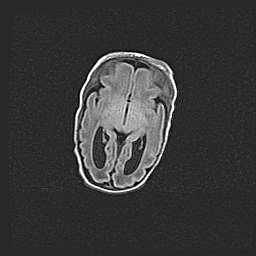

Мальформация Денди-Уокера. Киста задней черепной ямки.

Агенезия мозолистого тела.

Возраст: 2,5 месяца

Вес: 2420 г

Пол: женский

Окружность головы: 37 см

Срок гестации: 32 недели

Мальформация Денди—Уокера — редкий вид патологии ЦНС, представляющий собой врожденный порок развития каудального отдела ствола и червя мозжечка, ведущий к неполному раскрытию срединной (Мажанди) и латеральных (Лушка) апертур IV желудочка мозга. Для этогно синдрома характерна триада симптомов: гипотрофия червя мозжечка и/или полушарий мозжечка, кисты задней черепной ямки, гидроцефалия различной степени. В 70% случаев порок сочетается и с другими аномалиями головного мозга, в частности с агенезией мозолистого тела.